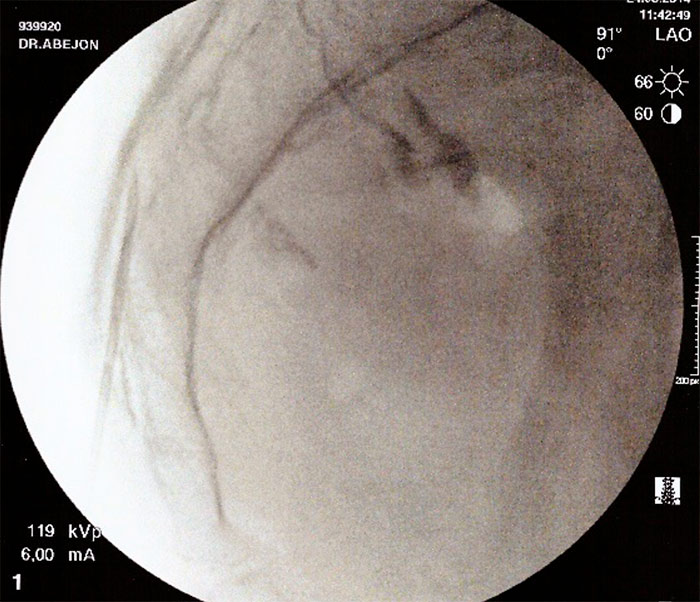

Se coloca al paciente en decúbito prono con una almohada debajo de la pelvis y con el arco de fluoroscopia en posición anteroposterior, se localiza el nivel a tratar. Para tratar S1y S2 se realiza una rotación axial del rayo para eliminar el doble contorno del disco L5-S1. Para S3 y S4 la posición del rayo es más vertical. Se debe colocar el haz de rayos en posición oblicua (10º) para intentar localizar el agujero sacro posterior (si no es posible, tratar de identificar el agujero sacro anterior, y el posterior suele coincidir con el borde superior). En esta posición se localiza el punto de entrada, se infiltra la piel con anestésico local y se introduce la aguja de radiofrecuencia en visión túnel (100mm con puntas activas de 5mm). Por último se coloca el arco de rayos en posición lateral y se introduce la aguja hasta el borde anterior del sacro y procedemos a la estimulación. Estimulación sensorial (50Hz): el paciente debe notar parestesias en el territorio de la raíz tratada entre 0.3 y 0.5v.

Estimulación motora (2Hz): debe provocar fasciculaciones motoras en el territorio afectado con un voltaje como máximo del doble del estimulo sensorial. Una vez localizado el GRDS se procede a realizar radiofrecuencia pulsada (45v durante dos ciclos de 120s, sin sobrepasar 42º). Una vez realizada la radiofrecuencia se inyecta contraste radiológico en tiempo real para descartar una punción intravascular y se administran anestésico local y esteroides.